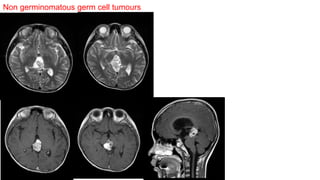

Nongerminomatous malignant germ cell tumors

• Adolescents : Peak incidence at 10-15 years of age.

• Prognosis : Poor , overall survival < 2 years.

• Tend to "hug" the midline.

• Differentiating intracranial germ cell neoplasms on the basis of imaging studies alone is difficult.

1. Yolk sac (endodermal sinus) tumour.

2. Embryonal carcinoma.

3. Choriocarcinoma.

4. Teratoma.

5. Mixed germ cell tumor.

Non germinomatous germ cell tumours